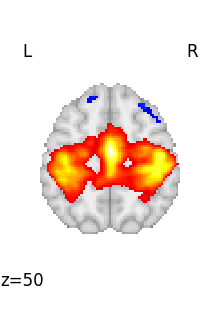

If we want to plot all the volumes in this 4D file, we can use iter_img to loop on them.

Then we give a few arguments to plot_stat_map in order to have a more compact display.

for img in image.iter_img(rsn):

# img is now an in-memory 3D img

plotting.plot_stat_map(

img, threshold=3, display_mode="z", cut_coords=1, colorbar=False

)